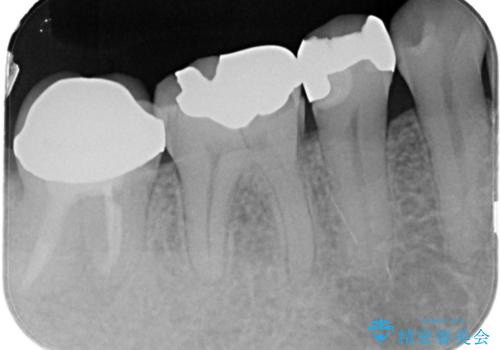

- 「硬い物を食べたら歯が割れた」を主訴に来院された患者さんです。

根っこのところまで歯が割れていたため、歯を残すことは不可能と診断し抜歯後、インプラントで治療を行いました。

破折の深さが歯根まで及んでいたため抜歯を行いました。

抜歯をしたあと骨が痩せないよう抜歯直後に骨補填材を入れています。